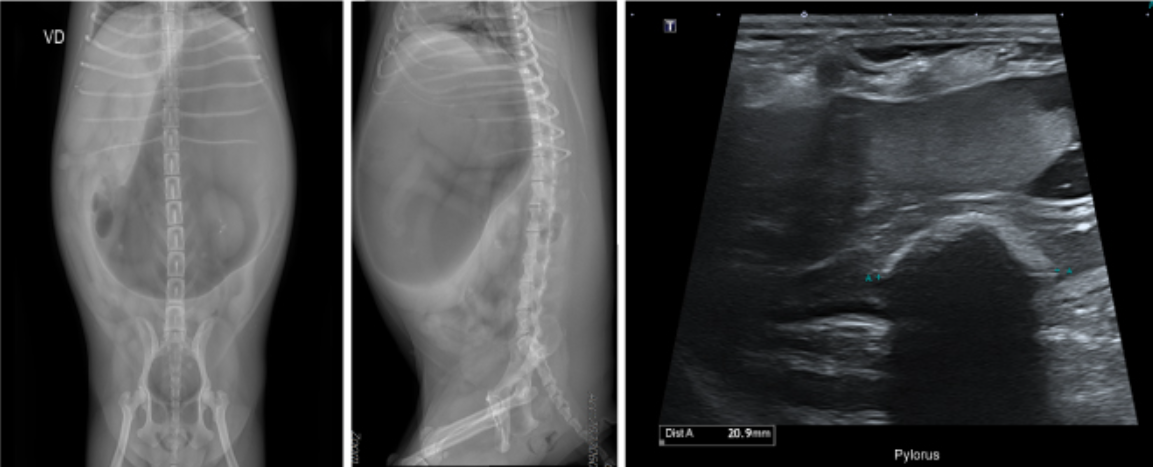

x-ray에서 심한 위 확장이 확인되었고 이로 인한 복부 팽만으로 판단되었습니다.

또한 추가적으로 진행한 복부 초음파 검사에서 위 유문부에 이물이 확인되었습니다.

초음파만으로 정확한 이물의 종류를 확인할 수는 없지만 형태상 씨앗류의 이물이 의심되었습니다.